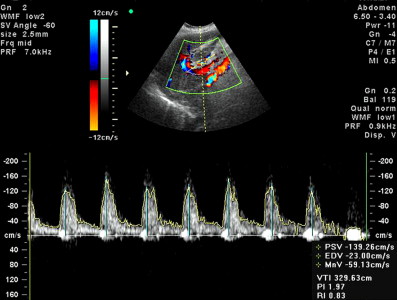

- проаналізує структури серця (камери, клапани, стінки передсердь, шлуночків, навколосерцеву сумку, швидкість руху крові)